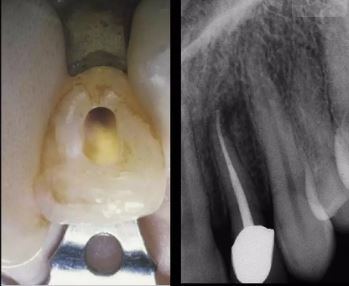

Răng cửa giữa hàm trên

Lỗ mở tủy được bắt đầu bằng cách đặt mũi khoan phía trên cingulum, gần như vuông góc với mặt trong của răng. Cingulum được chọn làm điểm bắt đầu vì, trái ngược với bờ nướu có thể co lại và bờ cắn có thể bị mòn, cingulum vẫn ổn định suốt đời của bệnh nhân (trừ bệnh nhân có mòn răng do acid và một số trường hợp khớp cắn sâu). Sau khi kết thúc giai đoạn thâm nhập, lỗ mở tủy vẫn chưa hoàn chỉnh, vì vẫn cần phải loại bỏ hai gờ cản, thường được gọi là “tam giác số 1” và “tam giác số 2” trong giai đoạn mở rộng. Hai tam giác này cản trở việc đưa dụng cụ nội nha vào đến mức đôi khi chúng có thể gần như ngăn chặn đưa dụng cụ vào.